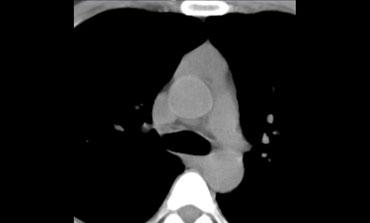

Hãy mô tả hình ảnh bên trái.

Sau đó tiếp tục.

CT cho thấy một khối nằm ở trung thất trước.

Khối có dạng nang nhưng có các thành phần đặc ngấm thuốc cản quang, do đó cần lo ngại đến u lympho, u tế bào mầm và u tuyến ức dạng nang.

Trường hợp này được xác định là u tuyến ức dạng nang.